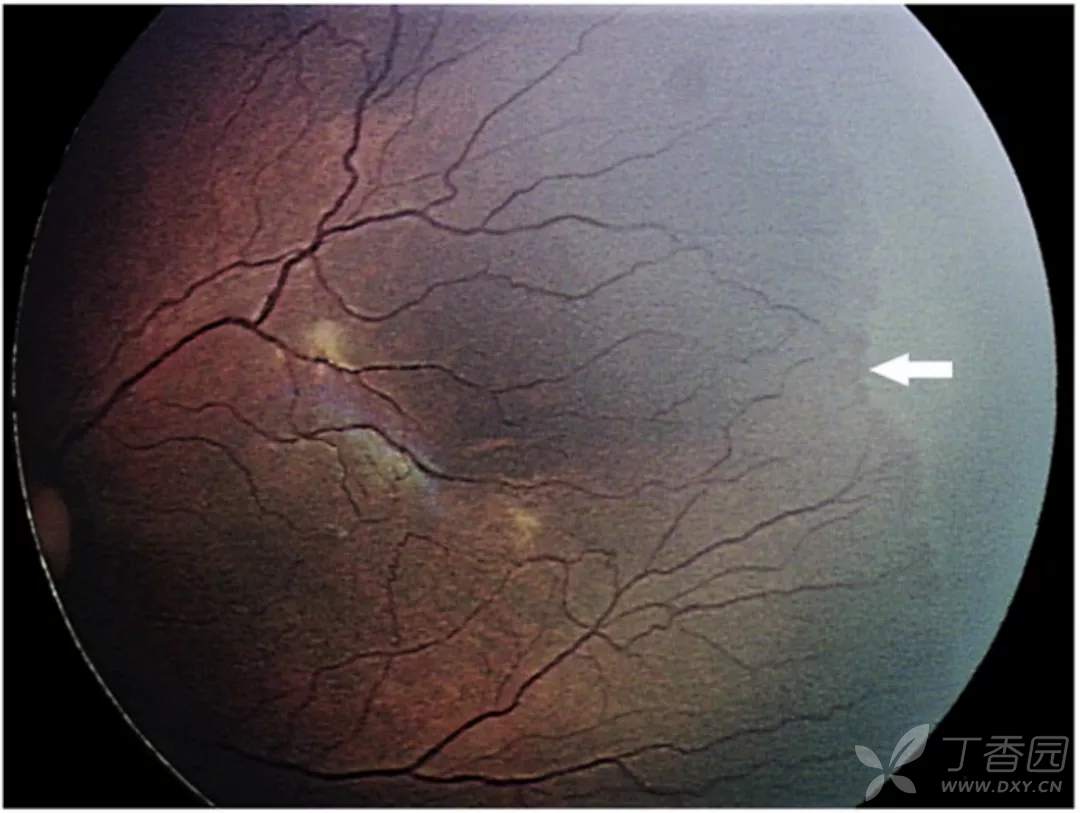

图. 4A期, 视网膜外新生血管牵引可导致视网膜隆起(白点),中心凹(星号)未见脱离,视网膜外新生血管(白箭)可能较脱离区更周边。

图. 4A期ROP,周边嵴区域出现360°牵引性视网膜脱离。